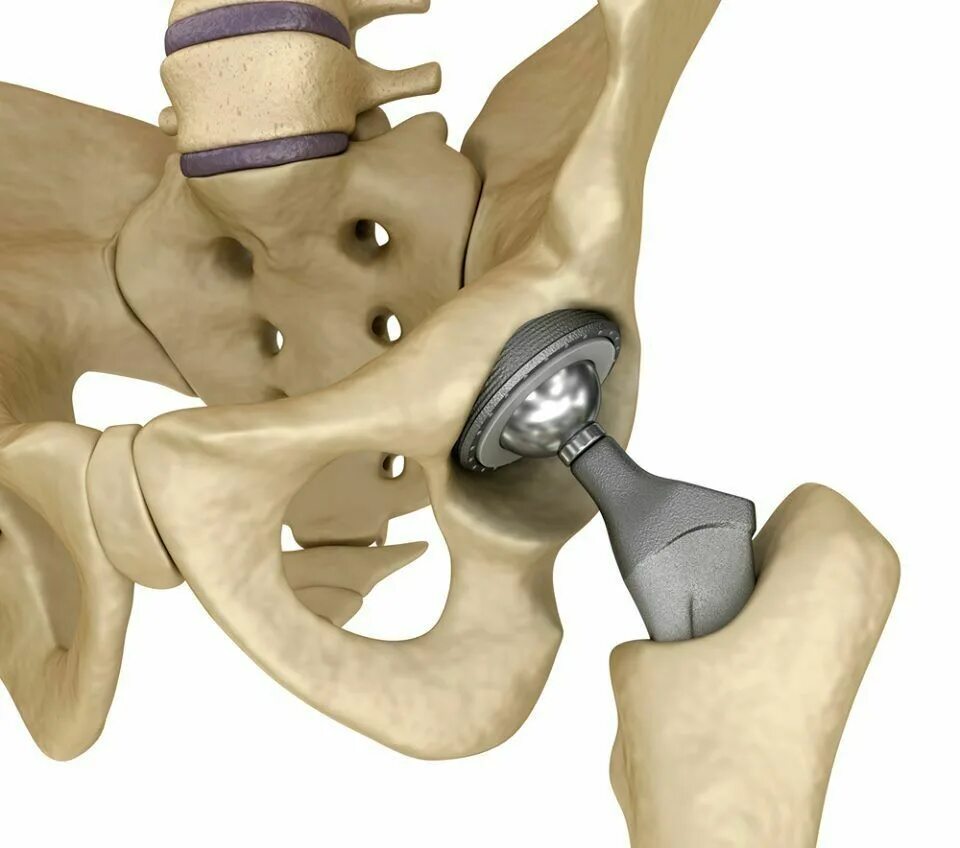

Протезирование суставов по квоте